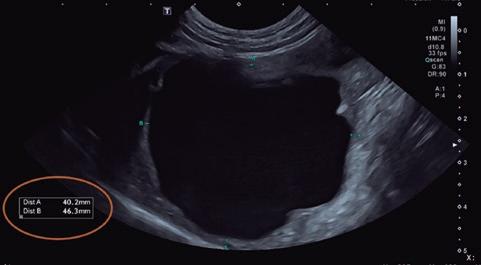

Estudio ecocardiográfico

• Modo B: en la proyección paraesternal derecha eje largo, se observó un jet de regurgitación mitral con dirección posterior y SAM (figura 3). En el eje corto derecho a la altura de la base cardiaca se observó un ratio atrio izquierdo/aorta (AI/Ao) de 1,92 (>1,6 se considera dilatación AI) (figura 4). Además, se observó hipertrofia de la pared del septo interventricular (SIV) de 7,6 mm y la pared libre del ventrículo izquierdo (PLVI) la 8,4 mm (hipertrofia >6 mm) (figura 5).

• Modo M: en paraesternal derecho eje corto a nivel de músculos papilares se observó un aumento del grosor del SIV en sístole (SIVs) de 7,8 mm (hipertrofia >6 mm), así como una hipertrofia de los músculos papilares (figura 6). • Modo Doppler: en la proyección paraesternal izquierda apical cuatro cámaras se midieron los flujos mitral (onda E 0,89 m/s y onda A 0,66 m/s) y subaórtico (4,56 m/s) (figura 7) ambos turbulentos, pero con velocidades dentro de rango. Presencia de ODTSVI. El flujo dentro de la aurícula izquierda estaba ligeramente disminuido (0,23 m/s, rango <0.25 m/s), aunque sin smoke

8. Proyección optimizada para la aurícula izquierda. En ella, se toma una de las varias medidas del flujo de sangre a este nivel para evaluar la predisposición del animal a sufrir un proceso trombótico (TEA).

(figura 8). Se observó un patrón de flujo transmitral pseudonormal.